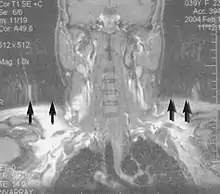

Magnetic resonance angiography (MRA) generates pictures of the arteries to evaluate them for stenosis (abnormal narrowing) or aneurysms (vessel wall dilatations, at risk of rupture). MRA is often used to evaluate the arteries of the neck and brain, the thoracic and abdominal aorta, the renal arteries, and the legs (called a "run-off"). A variety of techniques can be used to generate the pictures, such as administration of a paramagnetic contrast agent (gadolinium) or using a technique known as "flow-related enhancement" (e.g., 2D and 3D time-of-flight sequences), where most of the signal on an image is due to blood that recently moved into that plane (see also FLASH MRI).[47]

Techniques involving phase accumulation (known as phase contrast angiography) can also be used to generate flow velocity maps easily and accurately. Magnetic resonance venography (MRV) is a similar procedure that is used to image veins. In this method, the tissue is now excited inferiorly, while the signal is gathered in the plane immediately superior to the excitation plane—thus imaging the venous blood that recently moved from the excited plane.[48]